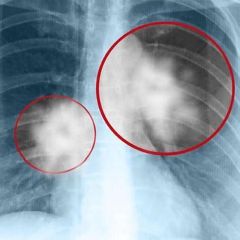

Среди злокачественных новообразований рак лёгких занимает лидирующие позиции в мире как по распространённости, так и по смертности. Вот уже более 30 лет он остаётся главным «онкологическим киллером». Мужчины болеют в 6 раз чаще, чем женщины. За последние 20 лет общая заболеваемость выросла более чем в 2 раза, при этом среди мужчин — на 51%, а среди женщин — на 75%. Есть и обнадеживающая статистика — на начальной стадии рак лёгких хорошо поддается лечению. Почти в 80% случаев после операции наступает стойкая ремиссия, и человек излечивается.

Но коварство рака лёгких состоит в том, что ранние его формы не имеют характерных клинических проявлений. Нередко больные длительно лечатся от других болезней, так как ранние симптомы рака лёгких часто не связаны с дыхательной системой. К ним относятся: субфебрильная температура (в пределах 37-38), слабость и усталость сразу после пробуждения, кожный зуд с развитием дерматита и появлением наростов на коже, слабость мышц и повышенная отёчность, нарушение работы центральной нервной системы: головокружение, нарушение координации движений или потеря чувствительности. Эти косвенные признаки могут присутствовать при многих заболеваниях, в том числе онкологических. Они могут быть при опухоли любой локализации. Их сочетание называется паранеопластический синдром.

Специфические симптомы, связанные с внутригрудным распространением опухоли — кашель с «ржавой» мокротой, одышка, кровохарканье, боль — чаще возникают при запущенной форме заболевания. В это же время появляются симптомы, связанные с внегрудным распространением опухоли. Они зависят от того, в каком органе появились метастазы.

Вторичная профилактика рака лёгких — это регулярные обследования, которые нужно проходить, чтобы выявить онкологию на ранней стадии, если она появится. Она необходима всем, для кого риск заболеть раком лёгких повышен. Ежегодно проходить обследование необходимо: курильщикам, людям старше 55 лет (особенно с заболеваниями органов дыхания или хроническими инфекциями), работникам вредных производств и людям, длительно проживающим в районах с экологически неблагоприятной обстановкой и с сильно загрязнённым воздухом. При профилактическом обследовании выполняют рентгенографию или компьютерную томографию лёгких. В России все взрослые люди ежегодно должны делать флюорографию. Это исследование проверяет состояние лёгких, но оно не выявляет рак на ранней стадии. Поэтому тем, кто находится в группе риска, нужно проходить дополнительное обследование. Его можно спланировать, обратившись к пульмонологу или к онкологу.